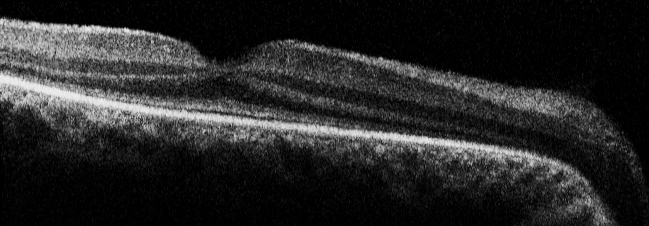

Figure 6 of Yzer, Mol Vis 2012; 18:412-425.

Figure 6. Spectralis OCT of the right eye of Patient 12 at age 9. Note the intact and normal thickness of all retinal layers.